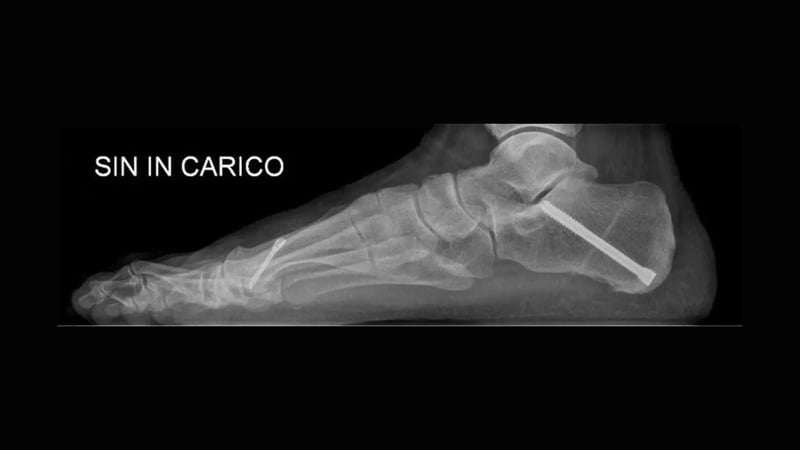

Tutto questo fa parte dell’anamnesi. Per prendere delle decisioni specifiche ci si baserà poi su radiografie eseguite in carico, cioè stando in piedi, per un'indagine di primo livello.

Infatti, è in posizione eretta che il piede lavora e fa male ed è in posizione eretta che va studiato. Questo è il motivo per cui una radiografia in carico offre spesso più informazioni di una risonanza magnetica (esame che si esegue sdraiati).

Tuttavia, oggi, la TAC in carico, come accennato sopra, è un esame fondamentale per diagnosticare un piede piatto che evolve e peggiora.

Si tratta di uno studio TAC eseguito con una tecnologia che permette di acquisire l’esame in piedi.

Tac in carico post-intervento, con assi di riferimento che mostrano la correzione delle deformità.